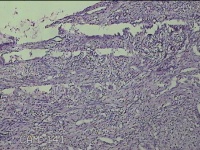

左大腿皮下结节

性别

女

年龄

30岁

临床诊断

皮下结节

一般病史

发现左大腿皮下结节1年余。

标本名称

大体所见

灰白粉红色组织1.7x0.8x0.3cm一个,表面带梭形皮肤 1.3x0.7cm,皮下见结节1.7x0.7cm一个,切开结节呈实性,切面灰白灰白粉红色,质中。

图3